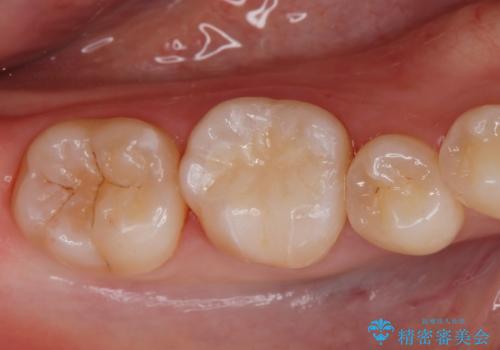

黒くなった奥歯をジルコニアクラウンに